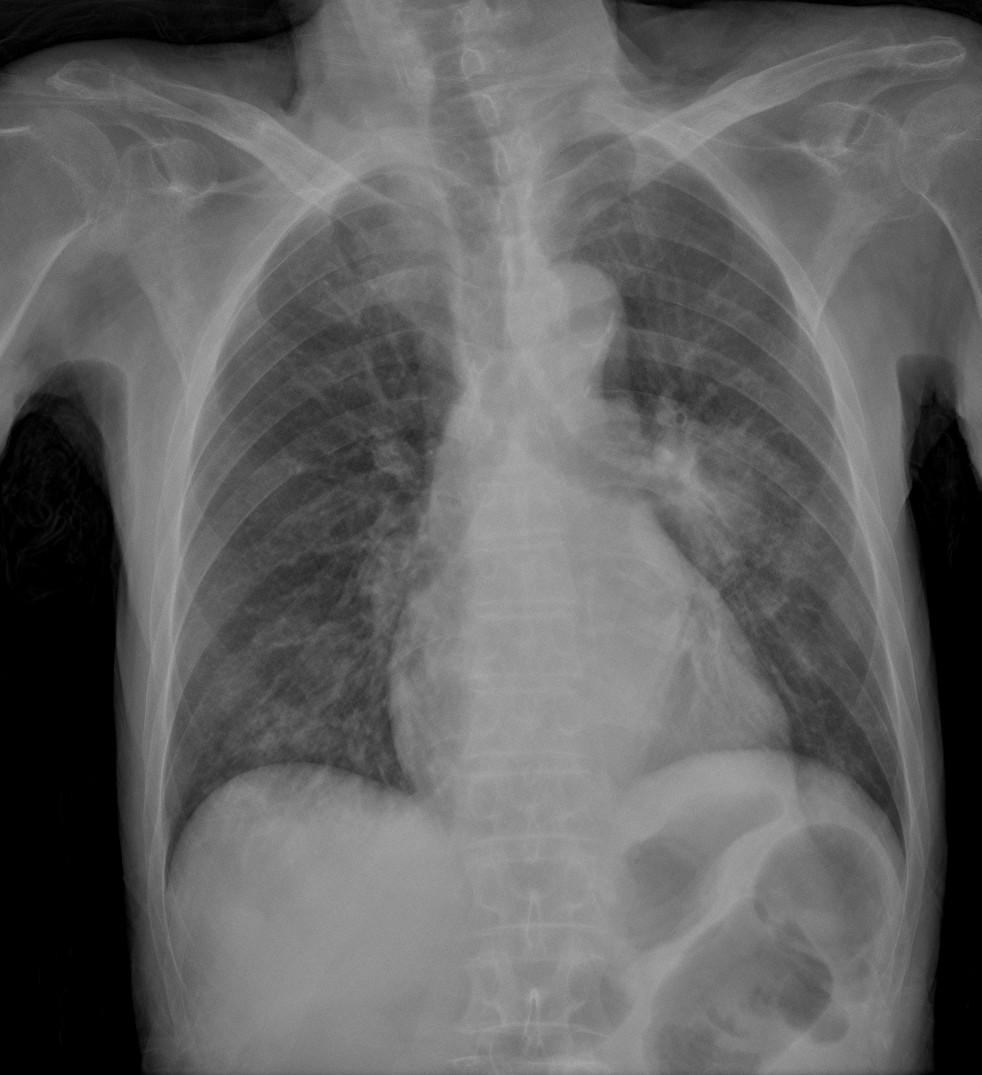

CASO: Operada de esofaguectomia y reconstrucción con coloplastia hace 3 meses. Sintomas de neumonía.

Hallazgos:

- De inicio llama la atención una densidad practicamente total del todo el hemitórax izquierdo, lo cual podría hacernos pensar que estamos ante una posible neumonía.

- Sin embargo el tórax está no está bien centrado, observar como la clavícula izquierda se encuentra casi en la mitad del pulmón, por tanto lo que vemos blanco es el mediastino ya que el tórax está rotado.

CENTRAJE:

El correcto centraje se determina comprobando que las extremidades internas de ambas clavículas equidistan de las apófisis espinosas vertebrales.

Mismo paciente, al cual esta vez se le ha tomado una radiografía en PA y en sedestación. Observar como las clavículas están equidistantes a las apófisis espinosas y como ha desaparecido el velamiento del pulmón izquierdo.

Por otra parte, paciente presenta una cardiomegalia y un discreto ensanchamiento del mediastino es probable relación con cambios postquirúrgicos.